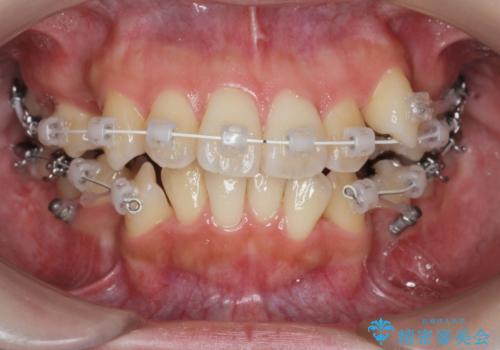

- ワイヤー矯正

- 八重歯・がたつきのある歯並びの改善を求めて来院されました。

全部の歯が入り切るスペースがなかったため、小臼歯4本を抜去しワイヤーを用いたマルチブラケット矯正を選択しました。

歯並びの改善と共に、歯ブラシがしやすくなった!と喜んでいただくことができました。